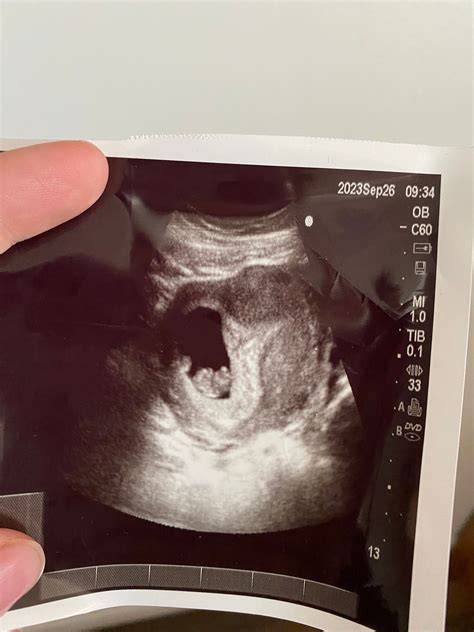

The nine-week ultrasound is typically performed between the eighth and tenth weeks of pregnancy. This scan is often transvaginal, providing clearer images of the uterus and the developing embryo. During this stage, the embryo is about the size of a grape, and several key developments are occurring.

• Embryo Size and Heartbeat: At nine weeks, the embryo is approximately 0.6 to 0.7 inches (15 to 18 millimeters) long. The heartbeat is usually visible and can be detected using Doppler ultrasound. The heart rate at this stage is typically between 120 and 160 beats per minute.

• Yolk Sac: The yolk sac, which provides early nutrition to the embryo, is visible and should be intact. This structure is essential for the embryo's development.

• Amniotic Sac: The amniotic sac, which contains the amniotic fluid that cushions and protects the embryo, is also visible. The fluid level is monitored to ensure proper development.

• Gestational Sac: The gestational sac, which houses the embryo and the amniotic fluid, is clearly visible. Its size and shape are assessed to confirm the pregnancy's viability.

• Crown-Rump Length (CRL): The measurement from the top of the embryo's head to its bottom. This measurement helps estimate the gestational age and due date.

• Heartbeat: The presence and regularity of the heartbeat are crucial indicators of the embryo's health.

• Yolk Sac: The yolk sac should be visible and intact. Its presence confirms the embryo's viability.

• Amniotic Sac: The amniotic sac should be clearly visible, and the fluid level should be adequate.